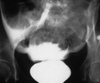

Q